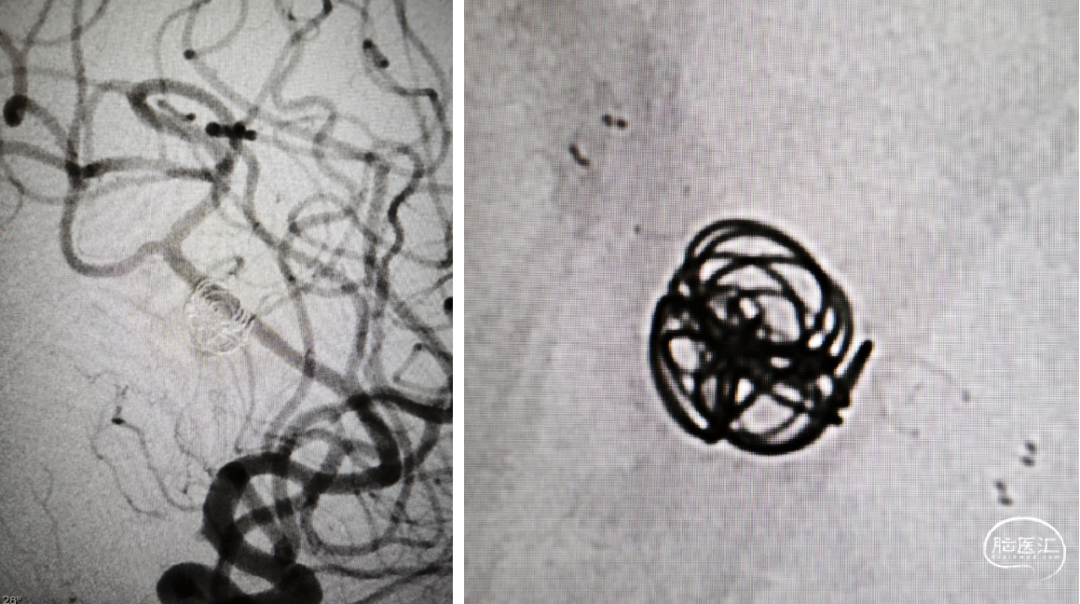

术后半年复查,动脉瘤消失,载瘤动脉通畅